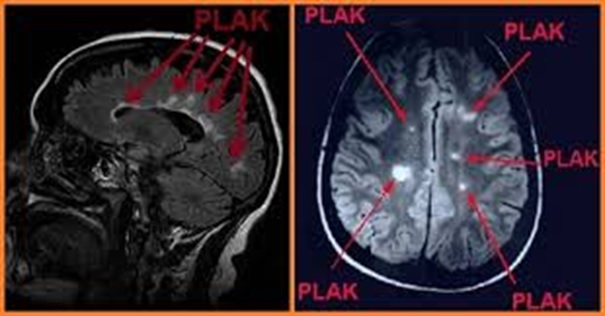

Multipl Skleroz (MS) merkezi sinir sisteminde pek çok yeri farklı ya da eş zamanlı olarak etkileyebilen bir hastalıktır. Hastalık; beyin ve omuriliğin hasarlı alanlarında sklerozan plaklar, yani sertleşmiş dokular oluşturur (RESİM 1). MS hastalığı daha çok 20 ila 40 yaşlar arasındaki yetişkinlerde görülmektedir. Daha erken veya daha ileri yaşlarda görülme olasılığı oldukça azalmaktadır.